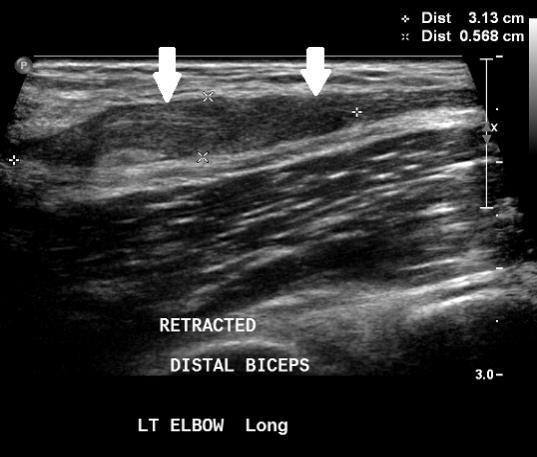

Fig. 4 Ultrasound showing biceps tendon retraction causing bunching and thickening of the torn tendon stump.

Fig. 2 Ultrasound showing normal biceps tendon (white arrows). Fig. 3 Ultrasound: The distal biceps tendon is ruptured. There is fluid and haematoma at the tendon defect (red arrow), and the tendon is retracted proximally (white arrow).

Ultrasound

Can confirm the tendon rupture and locate the tendon remnant

Fluid or haematoma may be seen in a measurable tendon gap